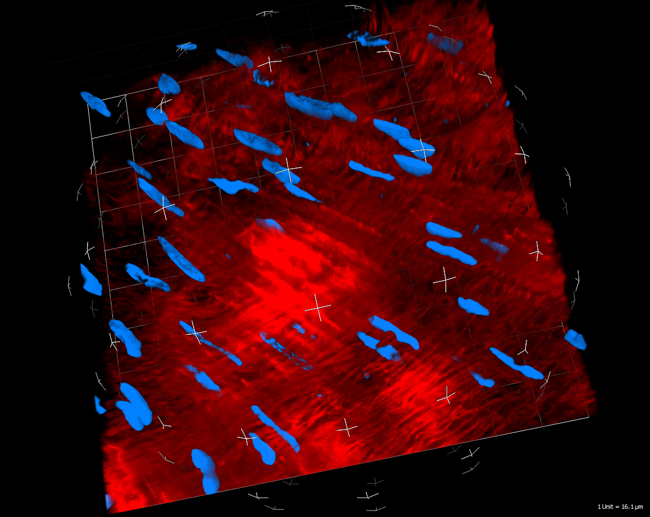

Simon Mathis, Gabriel Putzer, Martin Hermann, Lisa Schnegg, Judith Martini

A central objective of our group is to shed light on the endothelial glycocalyx and microcirculation during liver transplantation. It is already known that, during harvesting, storage on ice and subsequent reperfusion of the graft in the recipient, ischaemia reperfusion injury occurs with destruction of the glycocalyx, which is associated with poorer graft function and recipient outcome. With a new form of storage (normothermic machine perfusion), there is hope that the glycocalyx and therefore microperfusion of the graft will be better preserved. The working group is currently conducting two studies on this topic: a clinical study is investigating the effect of normothermic machine perfusion on the glycocalyx and the effects of endothelial glycocalyx shedding on perioperative organ function; an animal study is attempting to attenuate destruction of the glycocalyx through pharmacological adaptation of the perfusion solution during normothermic machine perfusion.

- Putzer, G.; Martini, J.; Gasteiger, L.; Mathis, S.; Breitkopf, R.; Hell, T.; van Enckevort, A.; Oberhuber, R.; Öfner, D.; Schneeberger, S.: Liver Transplantation Activity in the Eurotransplant Area Is Recovering Slowly During the COVID-19 Crisis. TRANSPLANTATION DIRECT. 2020; 6(11): e611.

- Cardini, B.; Oberhuber, R.; Fodor, M.; Hautz, T.; Margreiter, C.; Resch, T.; Scheidl, S.; Maglione, M.; Bösmüller, C.; Mair, H.; Frank, M.; Augustin, F.; Griesmacher, A.; Schennach, H.; Martini, J.; Breitkopf, R.; Eschertzhuber, S.; Pajk, W.; Obwegeser, A.; Tilg, H.; Watson, C.; Öfner, D.; Weissenbacher, A.; Schneeberger, S.: Clinical Implementation of Prolonged Liver Preservation and Monitoring Through Normothermic Machine Perfusion in Liver Transplantation. TRANSPLANTATION. 2020; 104(9): 1917-1928.

- Confocal microscope laboratory